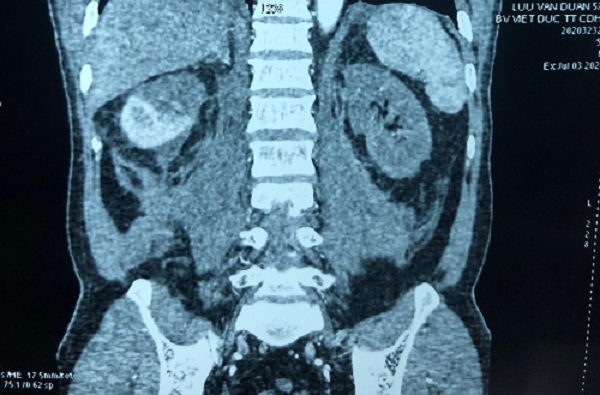

Ngày 1/3, bệnh nhi được ghép thận từ người cho sống, ca phẫu thuật kéo dài 8 tiếng.

“Trước đây, những bệnh nhân đã từng ghép thận không cần phải cắt thận nhưng với trường hợp cháu T., bác sĩ phải cắt cùng lúc 2 thận và tinh hoàn (bị loạn sản) 2 bên để tránh nguy cơ ung thư hóa thận và tuyến sinh dục, sau đó mới ghép thận cho bệnh nhi”, BS Dũng thông tin.

Một khó khăn nữa là bệnh nhi đã bị vô niệu 2 năm nay nên bàng quang rất nhỏ, chỉ tương đương với trẻ 1 tuổi. Niệu đạo đã từng mổ nên rất khó khăn khi đặt ống dẫn lưu theo dõi nước tiểu sau ghép. Tuy nhiên, sau nhiều giờ nỗ lực, ca phẫu thuật đã thành công.